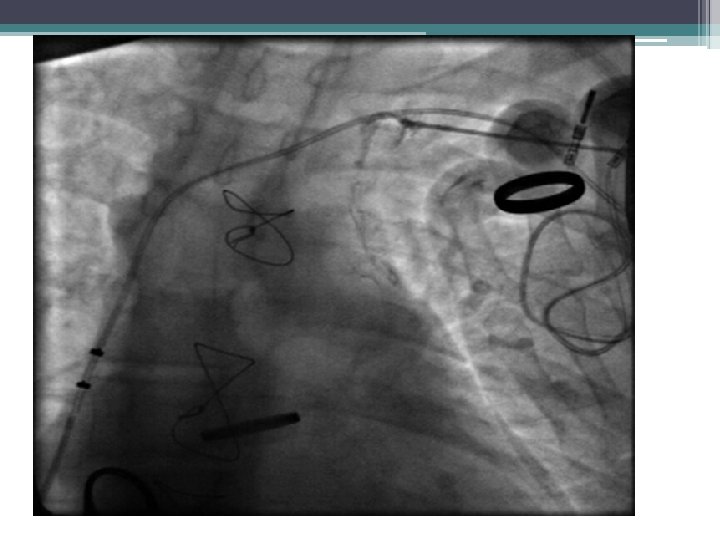

17 year old boy with postop FT. One abandoned TV lead. History of fever